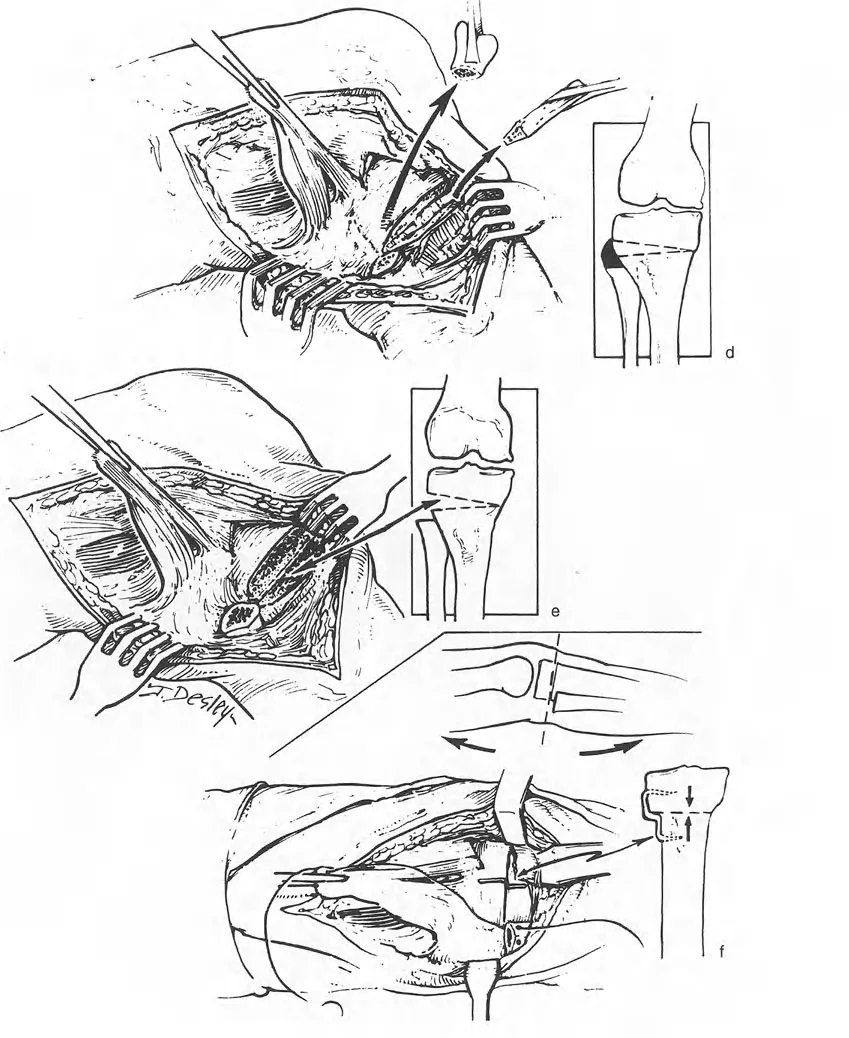

كان فريدريش باولز (Friedrich Pauwels) في الثمانينيات من أوائل الجراحين الذين أدركوا الأهمية العميقة للميكانيكا الحيوية وعلاقتها المباشرة بالتخطيط الجراحي لتصحيح التشوه عبر قطع العظم. لقد أ